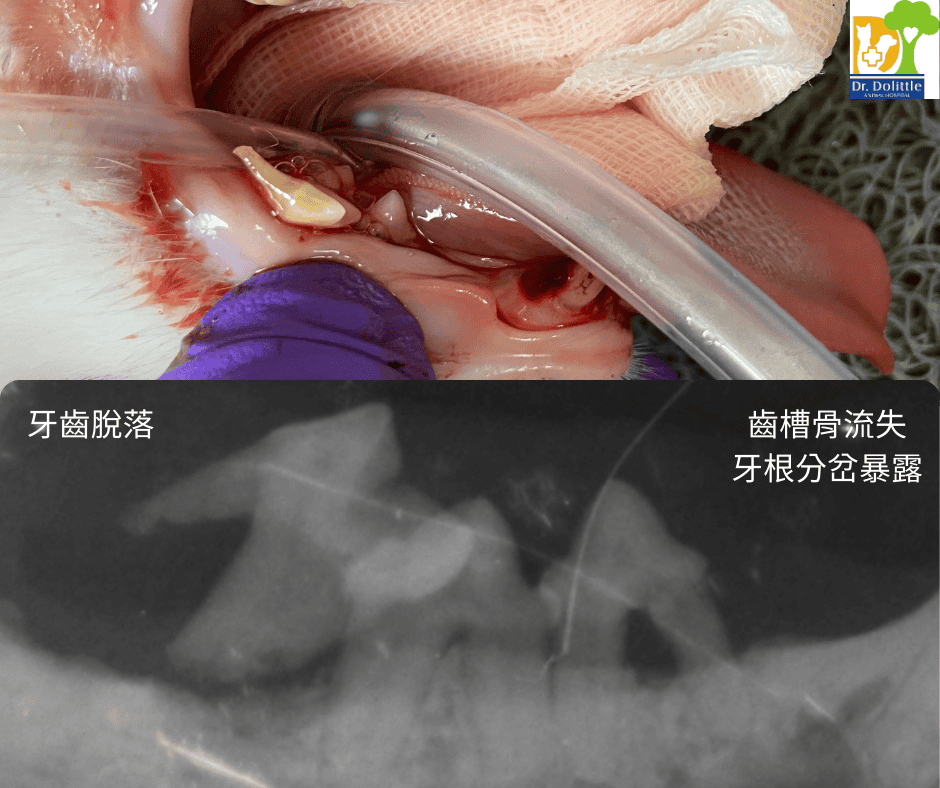

• 約 60-70% 的牙科問題(如牙根膿腫、齒吸收、牙周骨流失)藏在牙齦下,肉眼看不見,必須靠 X 光診斷。

4. 拔牙/牙周治療

• 若 X 光顯示牙齒無法保留(如嚴重牙周病、牙根尖膿腫、貓咪齒吸收),需進行拔牙手術。

• 拔牙傷口依據位置、大小進行傷口縫合,傷口較大會進行牙齦皮瓣縫補。